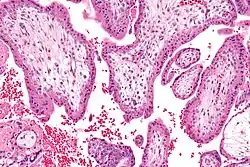

Durante el embarazo, las mujeres pueden someterse a pruebas de detección mediante una muestra de vellosidades coriónicas y amniocentesis para detectar la trisomía 16. Con el advenimiento de técnicas no invasivas para detectar aneuploidía, se puede utilizar la detección prenatal con pruebas que utilizan secuenciación de próxima generación antes que las técnicas invasivas. Esto puede causar retraso en el crecimiento fetal.[7]